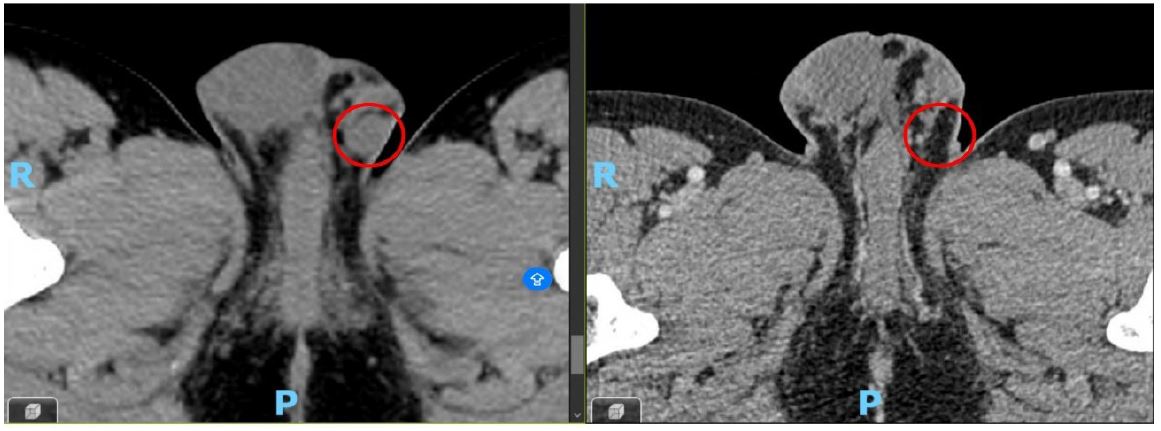

At the first reassessment after four cycles of selpercatinib, a response was observed, marked by a significant reduction in tumor mass and disease stability confirmed by subsequent imaging (Figures 4 & 5).

Figure 5: The left image depicts the testicular lesion at diagnosis (May 2023), while the right image illustrates its resolution following 13 cycles of selpercatinib (January 2025).